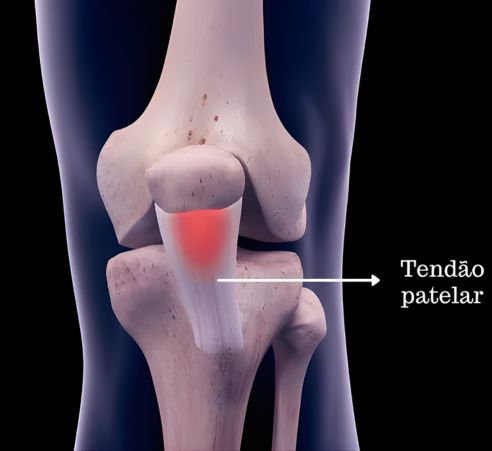

Você costuma sentir uma dor incômoda na parte da frente do joelho, logo abaixo da patela (a “rótula”), especialmente após praticar esportes que envolvem saltos ou corridas? Se essa dor persiste e parece piorar com a atividade, você pode estar sofrendo de Tendinite Patelar, popularmente conhecida como “Joelho de Saltador”. Essa condição dolorosa afeta o tendão que conecta a patela à tíbia, limitando o desempenho e impactando a qualidade de vida se não tratada adequadamente.

Para entender a dor, imagine o joelho de saltador não como uma lesão súbita e aguda, mas sim como um desgaste progressivo da cartilagem atrás da patela. A cartilagem, que deveria ser lisa e uniforme, torna-se amolecida, irregular ou com fissuras. Com o tempo, o atrito excessivo entre a patela e o fêmur (o osso da coxa) gera inflamação e dor, podendo levar a danos mais severos se não abordada.